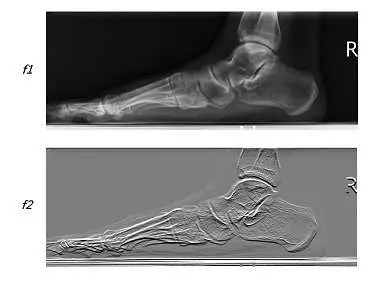

77.影像 f1 經過下列何者的運算可得到影像 f2 結果?

本題測驗醫學影像處理中的空間濾波(Spatial Filtering)與邊緣偵測(Edge Detection)。具體而言,探討透過卷積(Convolution)運算對影像進行梯度(Gradient)計算,以強化或萃取影像中特定方向的邊緣資訊,這在電腦輔助診斷(CAD)與影像強化技術中相當常見。

- 影像 (原圖):

- 為一張右腳的側位 X 光影像(Lateral Foot X-ray)。

- 影像右側包含一個標準的「R」字鉛字標記。

- 影像 (濾波後結果):

- 整體影像背景轉為中灰色,而結構邊界呈現一明一暗的浮雕效果(Embossing effect),這顯示該影像經過了一階微分(First-order derivative)或梯度濾波器的運算。

- 方向性觀察:影像中水平走向的邊界(如腳背邊緣、足底筋膜、蹠骨與趾骨的上下緣皮質骨)被強烈凸顯,呈現高對比的亮/暗線條。相對地,垂直走向的邊界(如跟骨後緣、腳跟後側軟組織、跗骨間的垂直關節面)則幾乎融入灰色背景中,沒有被強化。

- 關鍵細節(Letter "R"):「R」字的垂直主幹在 影像中完全消失,僅剩下其頂部與中段的水平筆畫。這是一個決定性的特徵,證明該濾波器